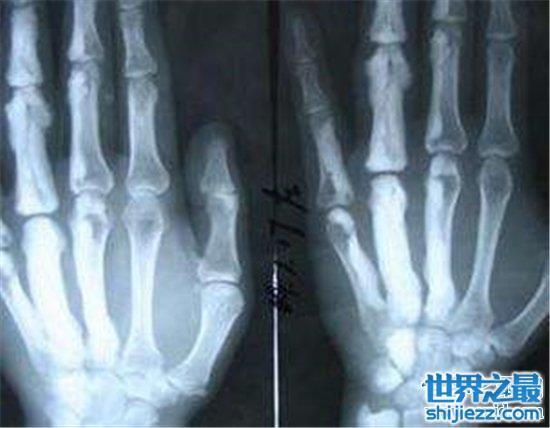

4、骨肉瘤

骨肉瘤是多发于年轻人群中的一种病症,主要表现在骨关节中增生的小肉瘤。而这个病症的诱因,重点就是我们对手机电脑等电子产品的长期使用,过度劳损手臂与肩膀等常用关节的后果显然是不容小觑的。万幸骨肉瘤在今天还是比较容易治愈,对人体健康的威胁也并不算大。